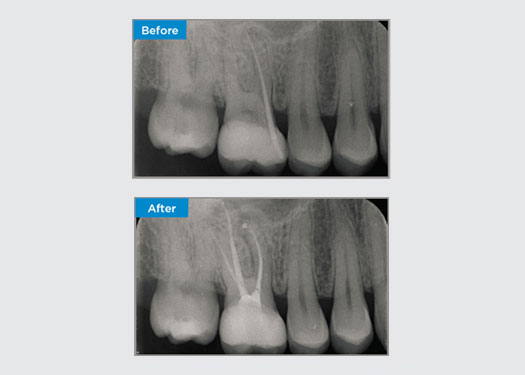

Patiënt presenteerde zich met asymptomatische apicale parodontitis op tand 34. Op basis van de preoperatieve röntgenfoto werd tand 34 opgemerkt met twee zichtbare wortels. Een CBCT-scan bevestigde echter een driewortelige premolaar en de kanalen waren in drieën verdeeld bij de middenwortel. Een zorgvuldige selectie van bestanden is cruciaal voor deze delicate tand.

Dr. Jack Lin, endodontist, Sydney, NSW Australië

In deze situatie is het behoud van de tand-/wortelstructuur essentieel om het risico op richels, transport, ritsen, perforatie en wortelbreuk te verminderen. Casusselectie, diagnose en planning vóór de behandeling zijn belangrijk. Endodontische vijlselectie met flexibiliteit, efficiëntie en respect voor de natuurlijke wortelanatomie is van cruciaal belang.